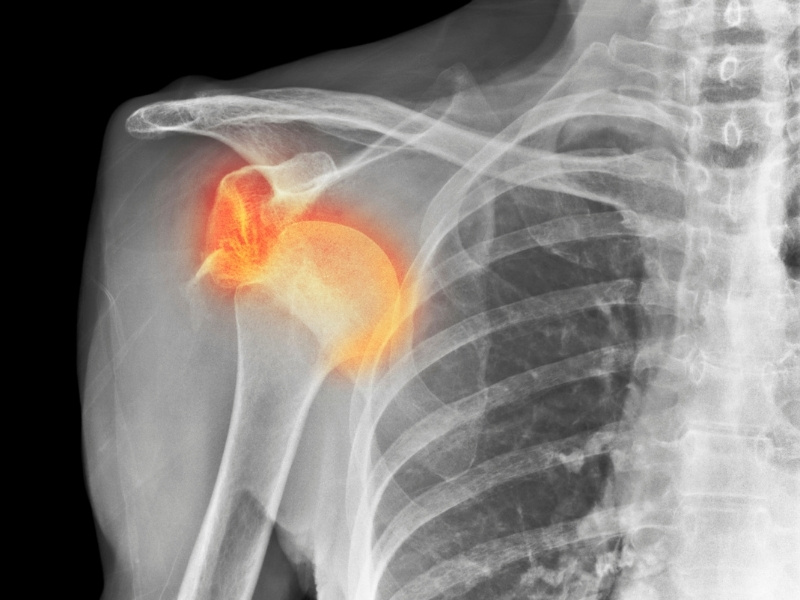

Omuz Problemleri Tedavileri

Omuz vücudun en hareketli eklemlerinden biridir ve günlük yaşamda yük taşımak, yazı yazmak, spor yapmak gibi bir çok aktivitede kullanılır. Omuz problemleri yaşam kalitesini önemli ölçüde düşürebilir.

Omuz rahatsızlıkları içinde en çok görülenler rotator cuff (manşet) yırtıkları, donuk omuz ve omuz çıkığıdır.

Omuz ağrısı yaygın olarak görülür ve pek çok nedeni olabilir. Yaşlanma, aşırı kullanım, spor yaralanmaları, romatizmal hastalıklar omuz ağrısı yapabilir. Kesin nedeni belirlemek için Ortopedi doktoruna başvurulmalıdır.

Omuz ağrısının tedavisi ağrının nedenine ve şiddetine göre değişir. Hekim kontrolünde ilaç tedavisi, fizik tedavi uygulamaları, egzersizler veya cerrahi müdahale gerekebilir.

Cerrahi tedavi kararı problemin ciddiyetine ve ameliyatsız tedavilere verilen yanıta bağlıdır. Tekrarlayan omuz çıkıkları, büyük rotator cuff yırtıkları veya ciddi kireçlenme durumlarında ameliyat seçeneği değerlendirilebilir.